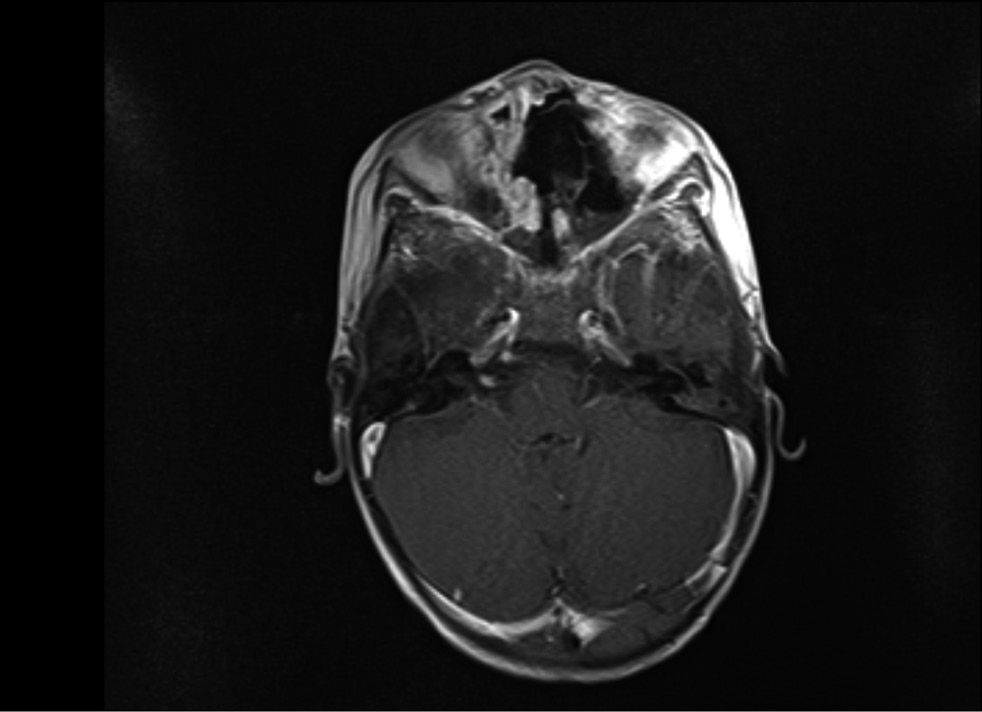

Рентгеновскую компьютерную томографию проводили в динамике на 36, 47, 63-й дни госпитализации. РКТ орбит и придаточных пазух носа выявила признаки множественных обширных очагов деструкции медиальных стенок орбит, костей носовой полости, твёрдого нёба, альвеолярных отростков верхнечелюстной кости, дефект мягкого нёба (рис. 4, 5). С помощью магнитно-резонансной томографии орбит, придаточных пазух носа, головного мозга на 63-й день госпитализации обнаружены признаки множественных обширных очагов деструкции медиальных стенок орбит, костей носовой полости, твёрдого нёба, альвеолярных отростков верхнечелюстной кости, дефект мягкого нёба (рис. 6, 7).

Рис. 6. Магнитно-резонансная томография орбит, придаточных пазух носа, головного мозга на 63-й день госпитализации в коронарной проекции.

Fig. 6. Magnetic resonance imaging of the orbits, paranasal sinuses, and brain in the coronary projection on the day 63 of hospitalization.

Рис. 7. Магнитно-резонансная томография орбит, придаточных пазух носа, головного мозга на 63-й день госпитализации в аксиальной проекции.

Fig. 7. Magnetic resonance imaging of the orbits, paranasal sinuses, and brain in the axial projection on day 63 of hospitalization.